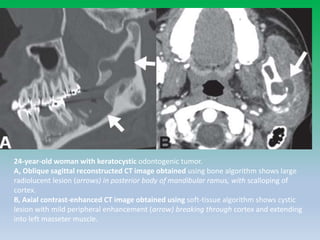

24-year-old woman with keratocystic odontogenic tumor.

A, Oblique sagittal reconstructed CT image obtained using bone algorithm shows large

radiolucent lesion (arrows) in posterior body of mandibular ramus, with scalloping of

cortex.

B, Axial contrast-enhanced CT image obtained using soft-tissue algorithm shows cystic

lesion with mild peripheral enhancement (arrow) breaking through cortex and extending

into left masseter muscle.